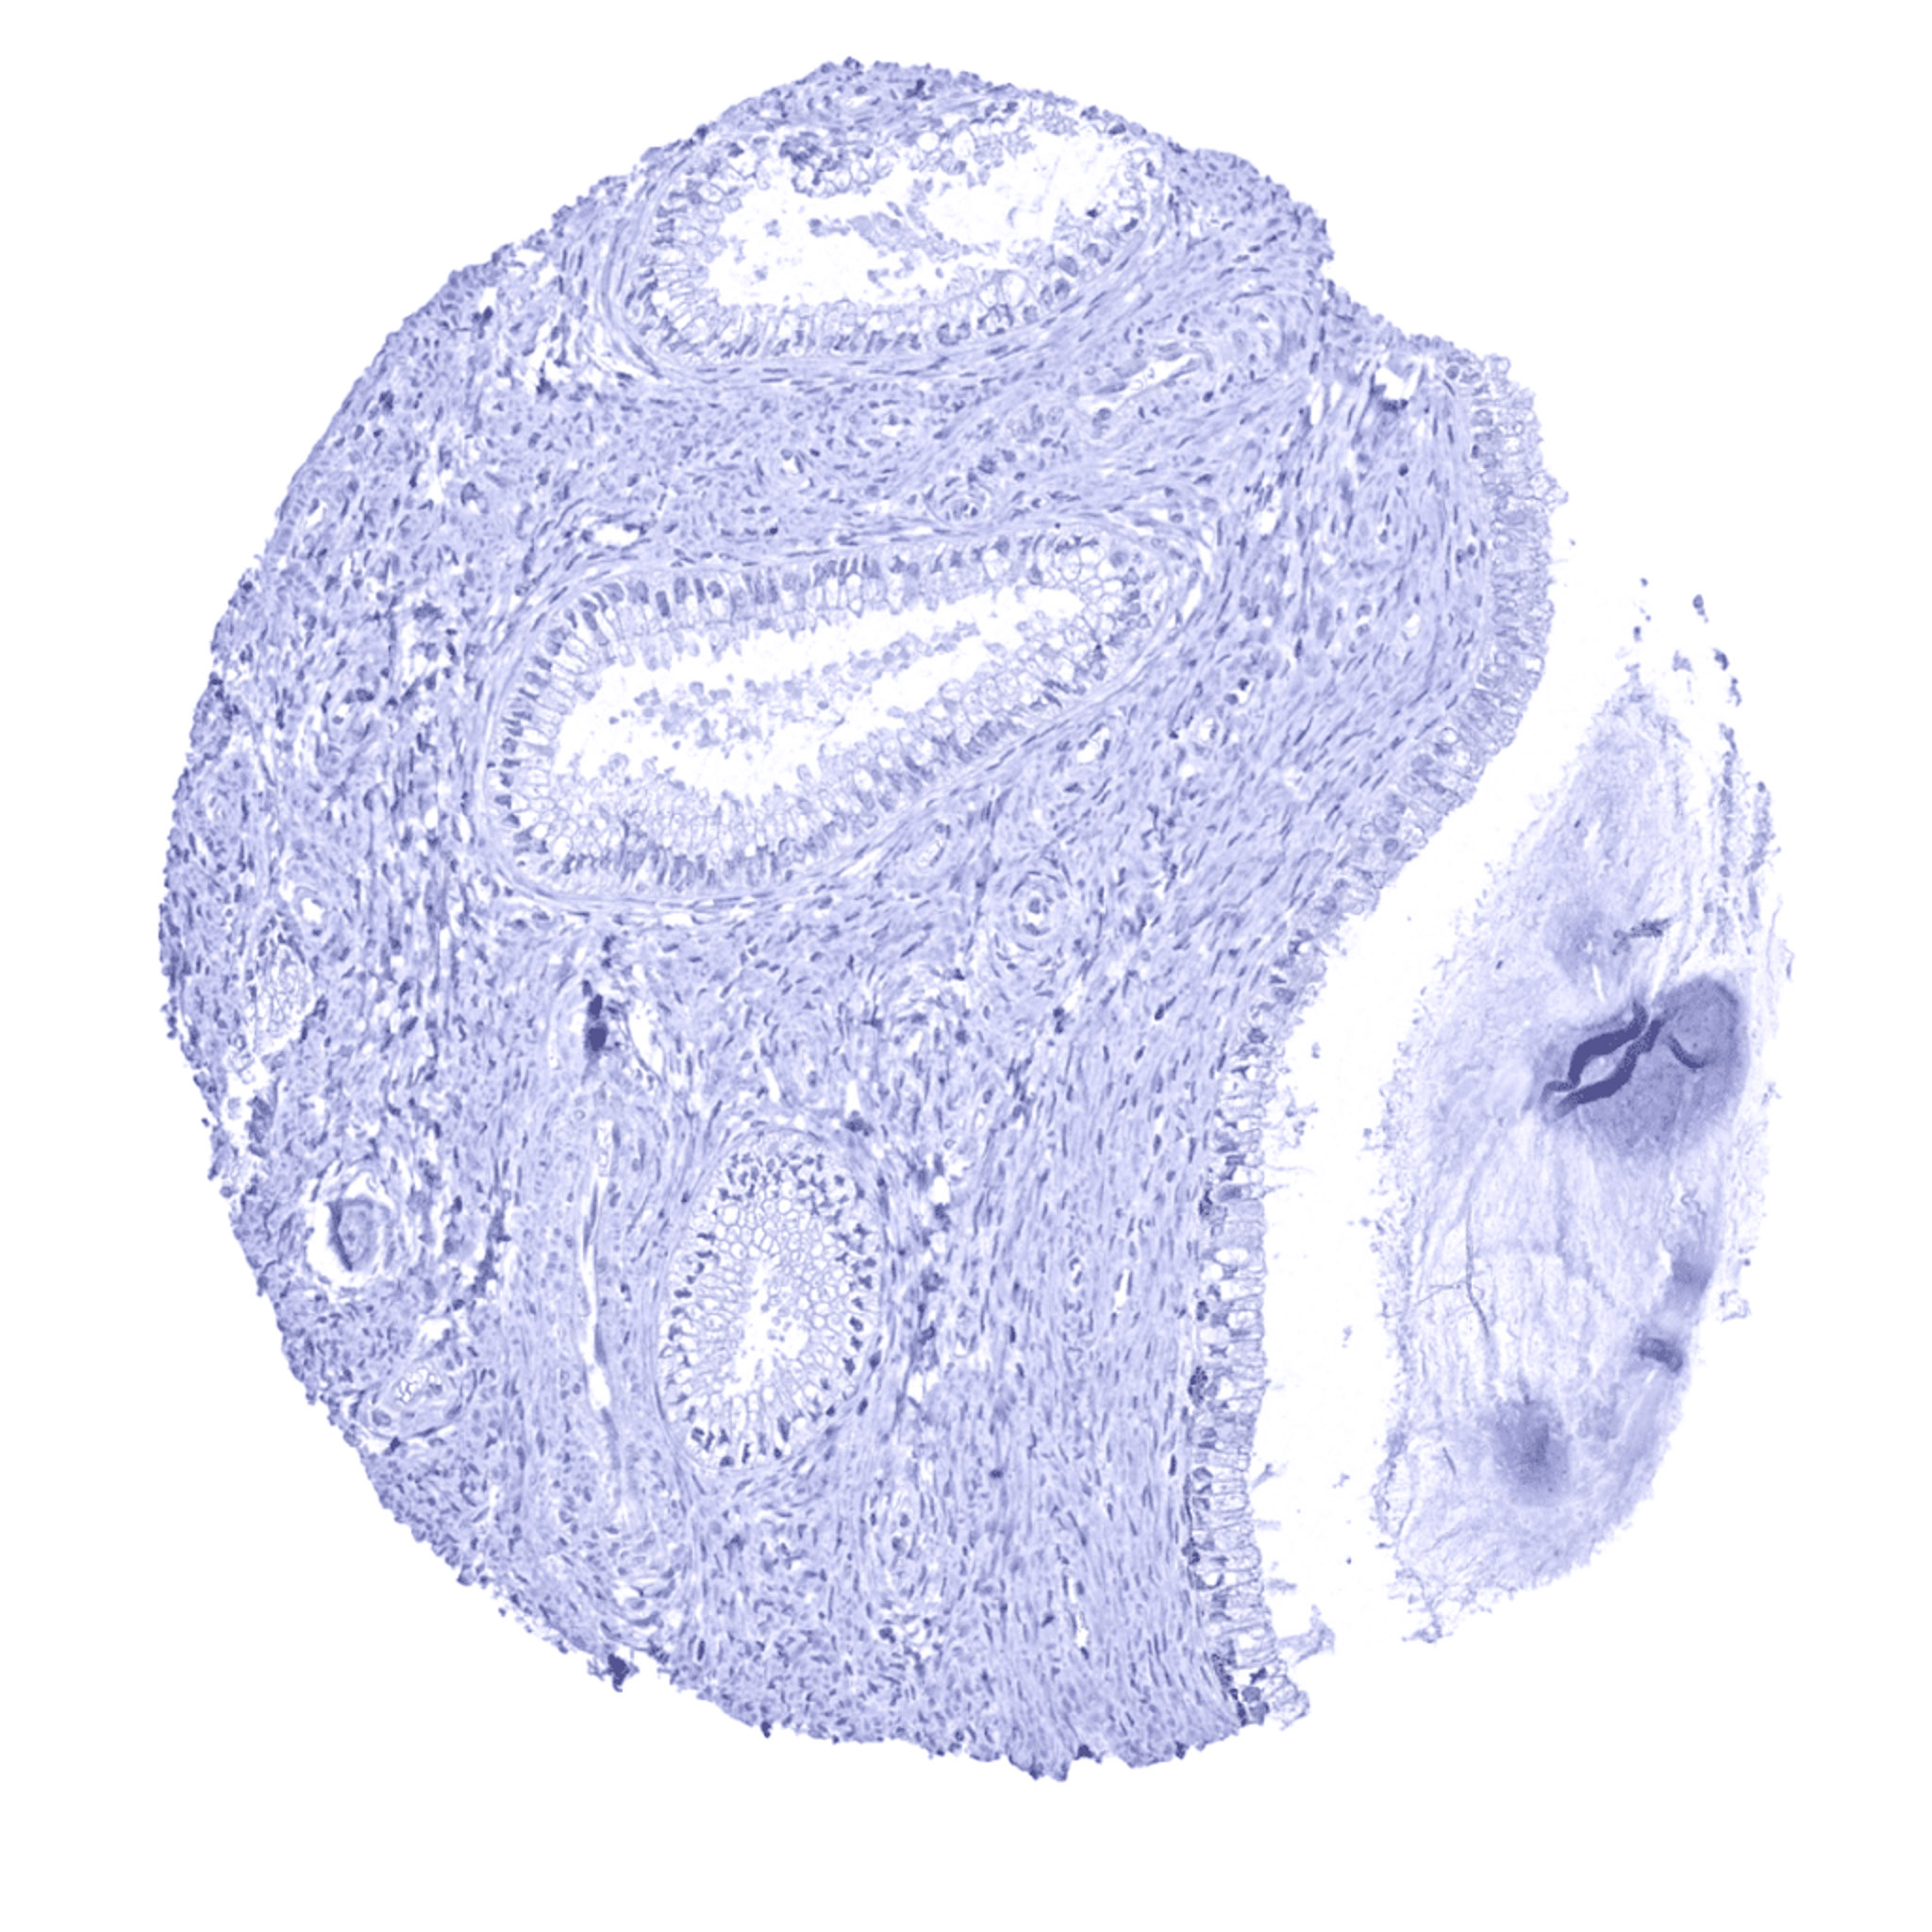

Appendix, mucosa – A weak to moderate TRIM29 staining can be seen in few crypt glands in this sample of the appendix.

Appendix, mucosa

Appendix, muscular wall